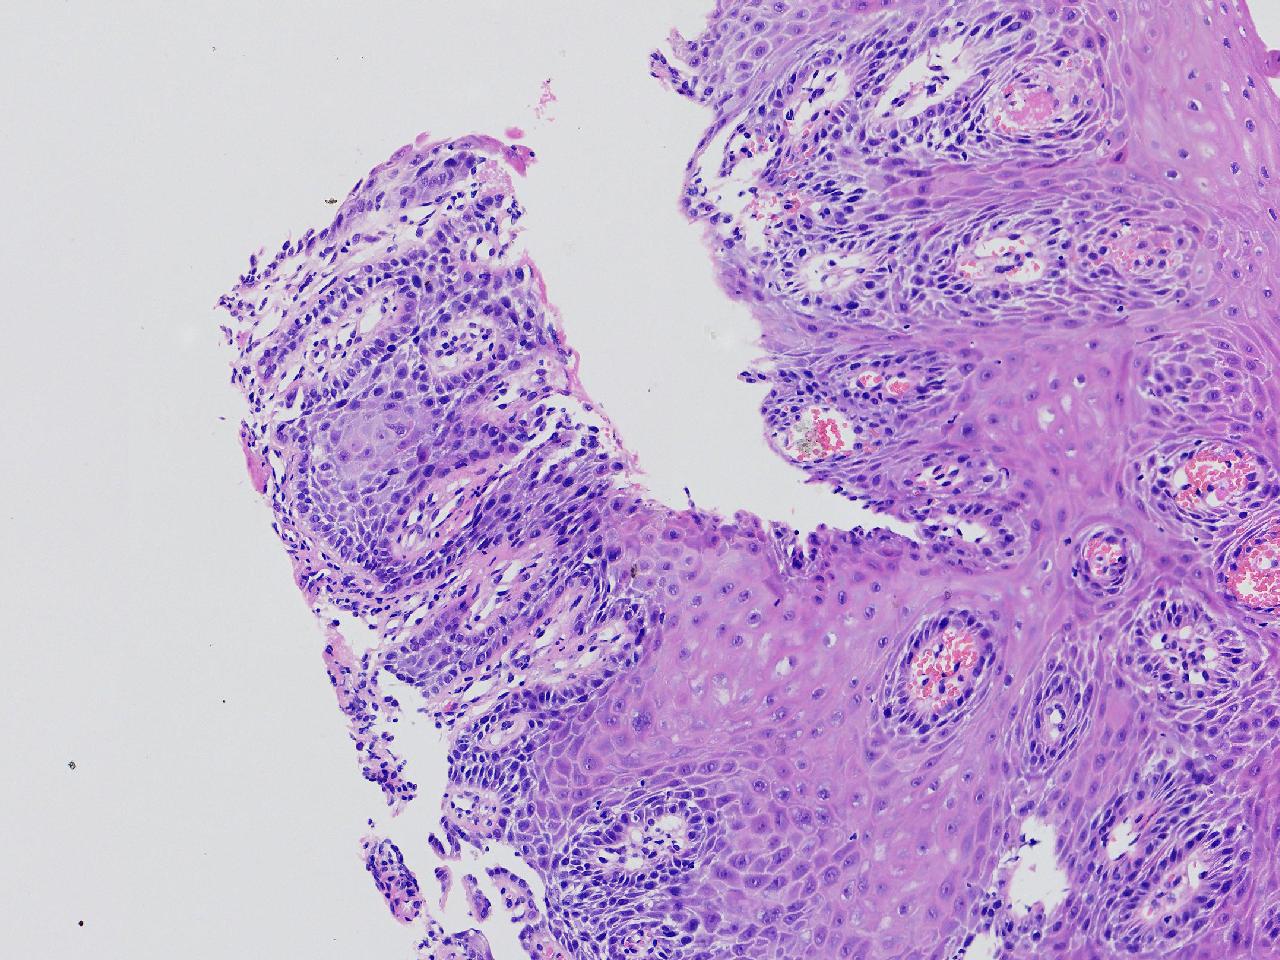

男,62岁,贲门口齿状线上见条状糜烂,活检1块,质软。

贲门口活检

灰白色不整形软组织1块,直径0.2厘米。

鳞皮乳头状增生伴慢性炎。